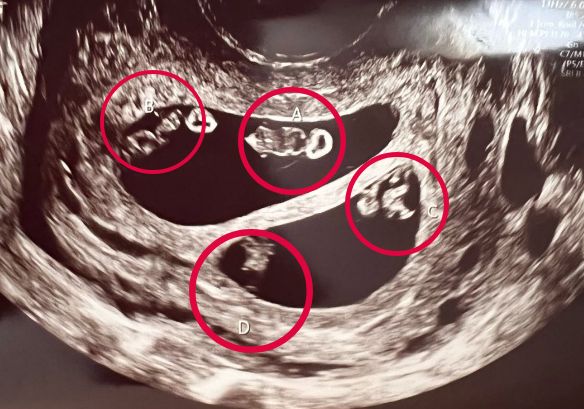

▲同時懷兩對雙胞胎的機率僅7000萬分之1。(圖/翻攝自IG)

美國一名孕婦到婦產科產檢時,醫生卻被超音波上的畫面給嚇傻了,因為她懷了「兩對」同卵雙胞胎,這個在醫學上的機率僅7000萬分之1。

內斯回憶起當時在產檢時的狀況,就連替她照超音波的醫生都感到非常困惑。第一次掃瞄時,醫生看著螢幕用筆寫上A跟B,內斯就興奮地問說,「我要生雙胞胎了嗎?」沒想到醫生卻起身走出房間說,「恩……我不知道,我要出去一會,確認一下狀況。」結果證實,內斯真的懷了兩對雙胞胎,一對男孩與一對女孩。

聽到這個消息後,內斯說她當下真的要暈倒了,尤其醫生又告訴她,這個機率僅7000萬分之1,「當醫生還在確認時,我就坐在那裡想說,好吧,我該怎麼做呢,我還怎麼告訴男友,我們即將生下四個孩子。」